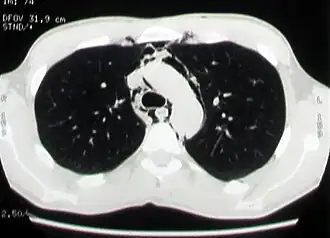

![]() КТ-изображение: эмфизема средостения у больного со спонтанным пневмомедиастинумом | |

Основными методами диагностики спонтанного пневмомедиастинума являются рентгенография грудной клетки в прямой и боковых проекциях и компьютерная томография органов грудной клетки. Другие инструментальные исследования, такие как рентгеноконтрастное исследование пищевода, фиброэзофагогастродуоденоскопия, фибротрахеобронхоскопия, электрокардиография, назначаются с целью исключения другой патологии, имеющей сходные клинические или рентгенологические проявления[1][8][22].

Компьютерная томография органов грудной клетки

Компьютерная томография является наиболее эффективным методом диагностики эмфиземы средостения, так как с его помощью легко выявляется наличие газа в средостении, на поперечных сечениях хорошо определяется его локализация и распространённость эмфиземы. Преимуществом перед рентгенографией является возможность диагностики пневмомедиастинума даже в тех случаях, когда имеется выраженная эмфизема мягких тканей грудной стенки, сводящая информативность рентгенографии в этой ситуации к минимуму. Кроме того, компьютерная томография позволяет провести дифференциальную диагностику спонтанного пневмомедиастинума и других заболеваний с похожей клинической картиной, а также важна для установления причины заболевания[2][21].